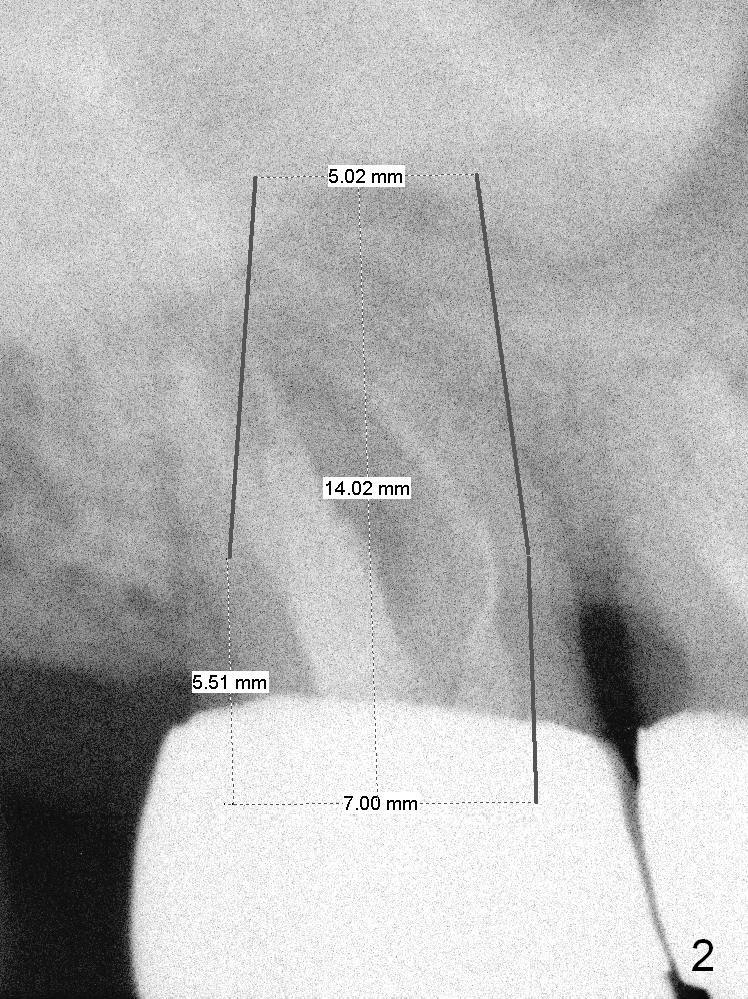

A 59-year-old man is a bruxer, fracturing the teeth #8 and 9. Now the tooth #2 seems to have fractured (Fig.1). Since the apices appear to protrude into the sinus, either 7x14 mm tissue-level (Fig.2) or 6.9x10 mm bone-level (Fig.3) implant will most likely penetrate the sinus floor (red dashed line). To protect the sinus membrane, PRF membrane or plug (blue curved line) is to be placed prior to bone graft (yellow circles) and implant placement. Prepare Magic Expanders and Magic Sinus Lifter. Clindamycin will be used after extraction. Since the roots of the upper 2nd molar usually fuse, prepare large gauzes for hemostasis. Check the buccal and palatal walls for any defect. Start osteotomy away from the defective wall. Place the remaining PRF membrane for wall repair before bone graft. Set stopper 2 mm short of the intended bone-level implant length.